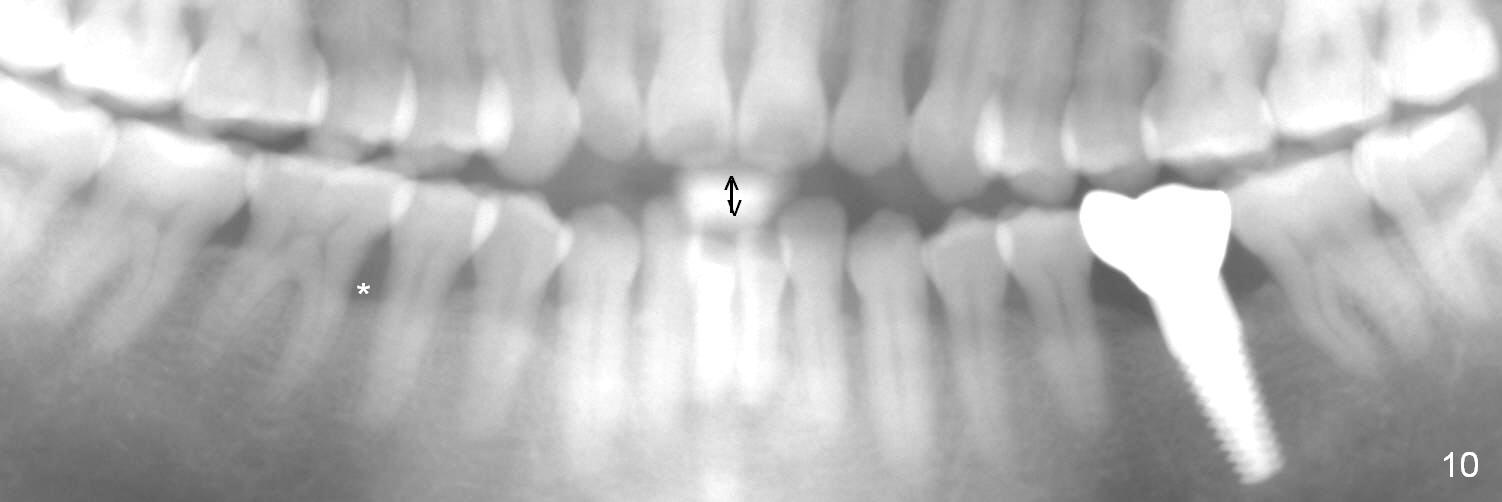

The mesial and distal crests of the tooth #19 were even for a 50-year-old man 7 years ago. Three years later, swelling developed around the distal root with bone loss (Fig.2 *). Three months later, localized swelling occurred (Fig.3 *) with oozing. The patient had thrombopenia (platelet 40 K). The tooth was extracted with suture. There is distolingual root tip resorption. Two months and a half later (Fig.4), a 6x17 mm implant was placed (Fig.5). The implant osteointegrated 5 months postop (Fig.6). The distal crest re-appears 5 months (Fig.7), 2 years (Fig.8) and 2 years 8 months (Fig.10) post cementation. At the last appointment, the patient complained of pain and swelling at #30 with mesial bone loss (Fig.10 *), as compared to Fig.9 taken 9 years ago. The mesiolingual pocket is deep. After scaling and Chlorhexidine irrigation, Arestin is locally administered.

It appears that the lower molars have a type of occlusal trauma. There is anterior open bite (Fig.10 double arrows).